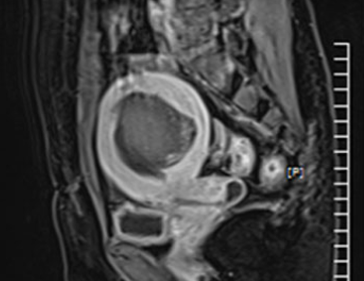

• 시술 전

시술 후